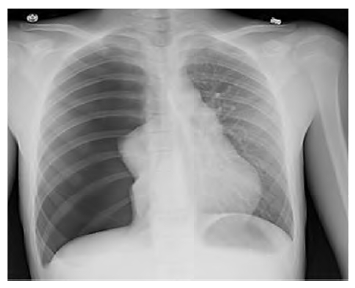

Após sofrer trauma de tórax contuso, determinado paciente de

35 anos de idade chega à emergência e relata que é motorista de

moto e colidiu contra um carro, com cinemática grave. Durante a

avaliação inicial, o paciente encontra-se alerta, conversando,

lúcido. A via aérea está prévia, ausculta pulmonar com murmúrio

abolido à direita, expansão torácica assimétrica, sem sinais de

choque ou instabilidade hemodinâmica, sem turgência jugular.

Ele apresenta abdome flácido e indolor, pelve estável, sem outras

alterações no exame físico. Os raios X de tórax a seguir foram

realizados na admissão do paciente em unidade hospitalar.

Com base nesse caso clínico hipotético e na imagem radiográfica apresentada, e considerando os conhecimentos médicos correlatos, assinale a alternativa correta.